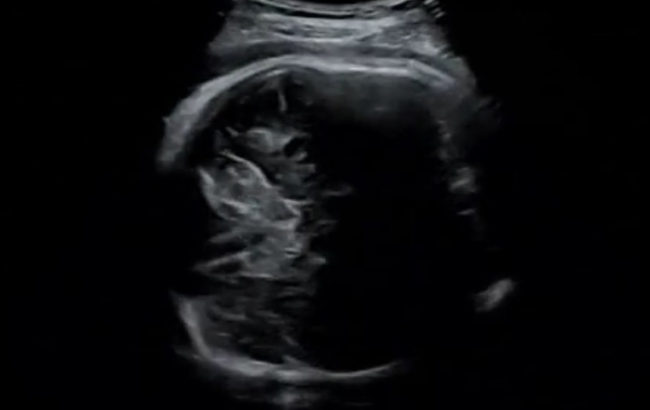

産後ケアのために

行政では「お産と育児の疲れから体調がよくない」、「手伝ってくれる人がいなくて不安」、「授乳が上手くいかない」など、育児等の支援が必要な方を対象に、心身のケアや育児のサポートを行い、安心して子育てができるように「産後ケア事業」を行っています。

このように行政も産後のケアに力をそそいでいます。「音響チェア」では産後の母親の身体のケアをしています。いちばん大事なのは上記のような子育て支援ではなく、母親の体調改善です。もとの身体に早く戻すこと身体や精神的に健康であればすべての不安から解消されます。1日でも多く体調を戻すために音響チェアをご利用下さい。

中国では「産後ケア病院」があり妊婦は1ヶ月入院し、自分の身体のケアを重視しています。